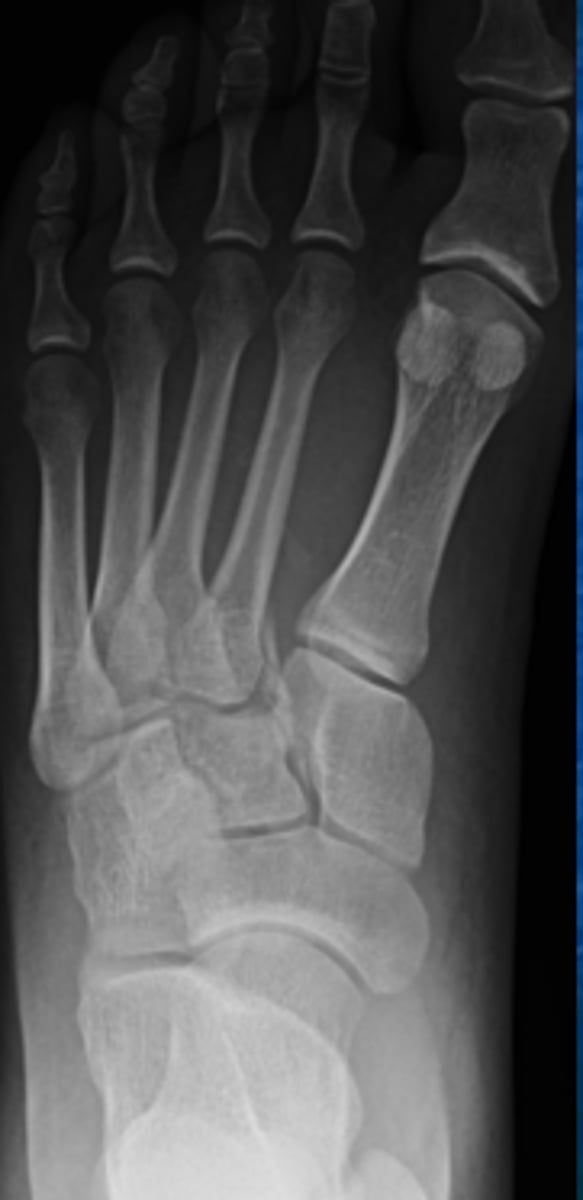

What type of fracture is this?

Answer

Lisfranc fracture

A fracture that doesnt heal well of the wrist and foot

Wrist=scaphoid

Foot=lisfranc